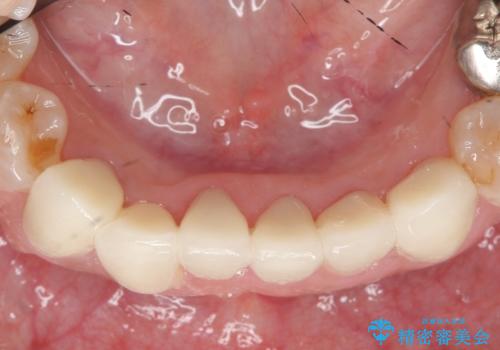

- 上下顎前歯部の見た目が気になるといらっしゃった方の症例です。

上顎は左4番から右4番までの8歯、下顎は左3番から右3番までの6歯、計14歯をオールセラミッククラウンにより補綴しました。